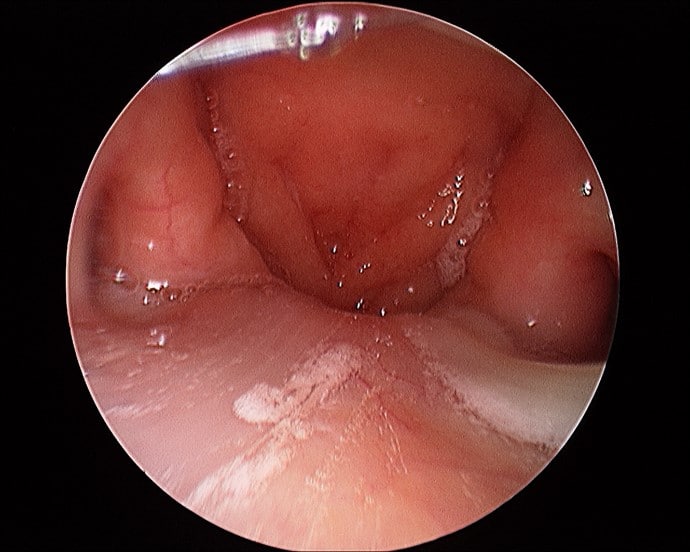

- 내시경 검사 : 코와 목의 내시경 검사를 통해 부비동의 상태 및 인후부의 염증을 진단합니다.